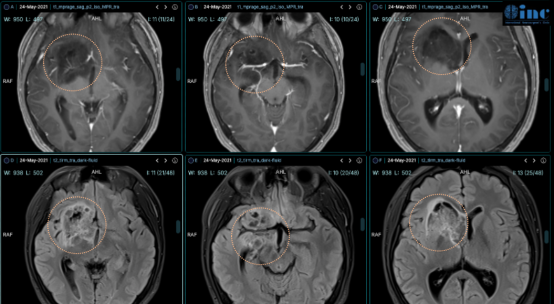

医生,我做了那么多磁共振检查,可以看出来我的胶质瘤是良性还是恶性吗?能不能确定哪一种级别胶质瘤?这是很多胶质瘤病友关心的问题。临床中常根据颅脑磁共振诊断肿瘤的位置、形态、...